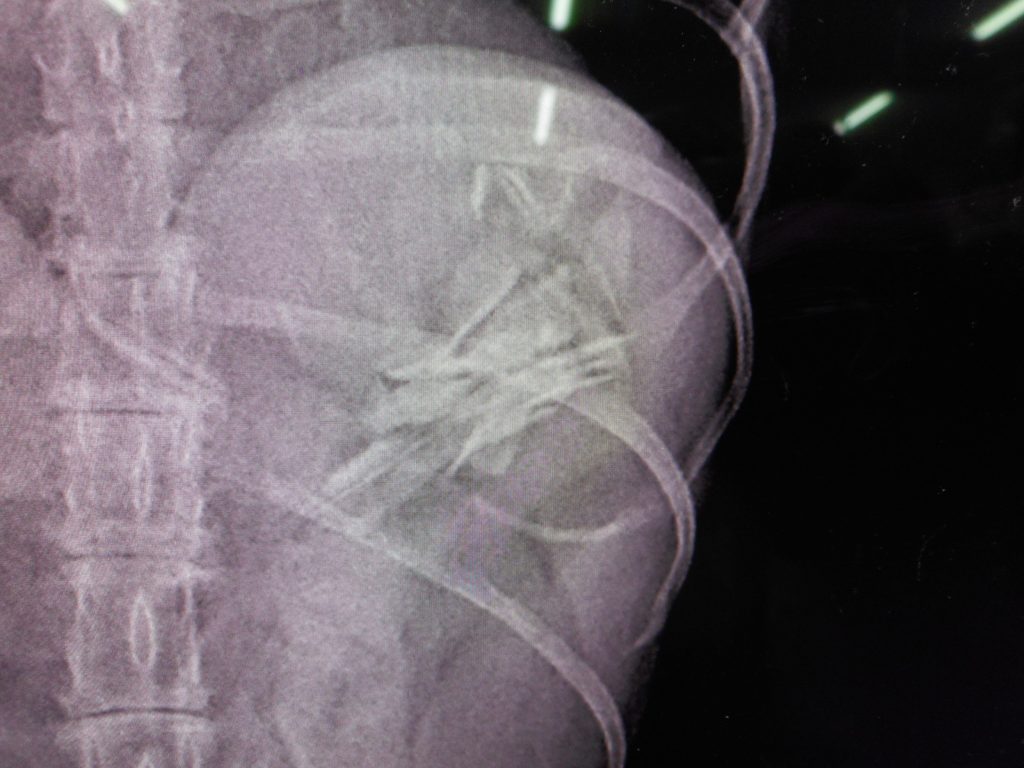

縦から診ると、

どこにあるか?

ココです